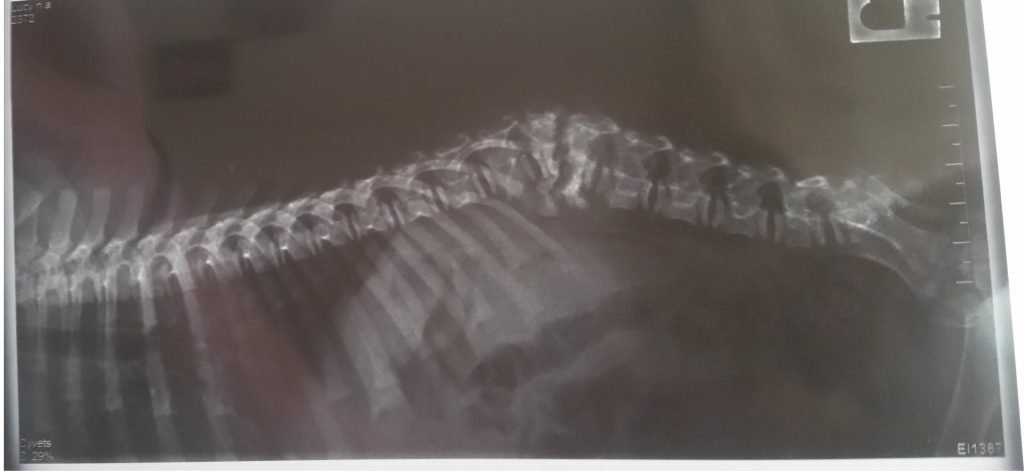

A avut coloana rupta, acum s-a sudat si are paralizie picioare spate.

În urma terapiei în apa și exercițiilor efectuate zilnic,piciorul stâng și-a revenit aproape complet,dar dreptul nu îl mișcã. Doctorul spune ca are nervul afectat. Rãspunde la stimuli. Nu merge, se târãște, ajutându-se de piciorul stâng. Nu are puncte dureroase. Mãnâncã foarte bine, nu are diaree, nici febra. Rãspunde la înțepãturi.

Va atașez radiografia .